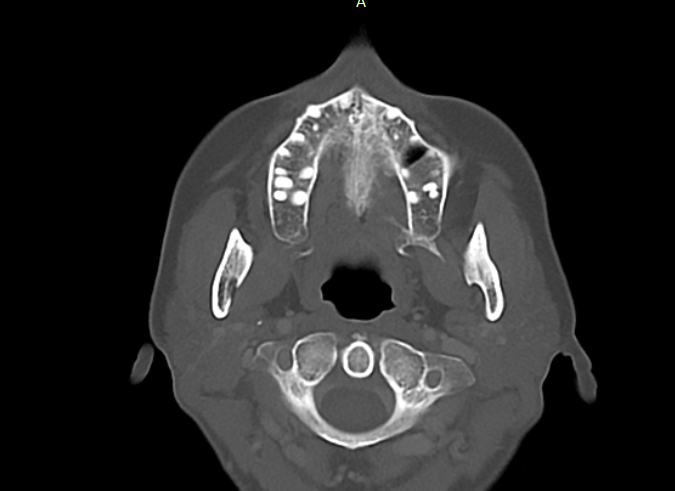

Hey there. So I’m attaching a Pic of the C1 you mentioned ( I think this is it ). What are your thoughts?

@Ihurt can you go up or down until you can see the full C1 tranverse process? I’ve attached mine to show what I mean. Just want to see the full wings of your C1.